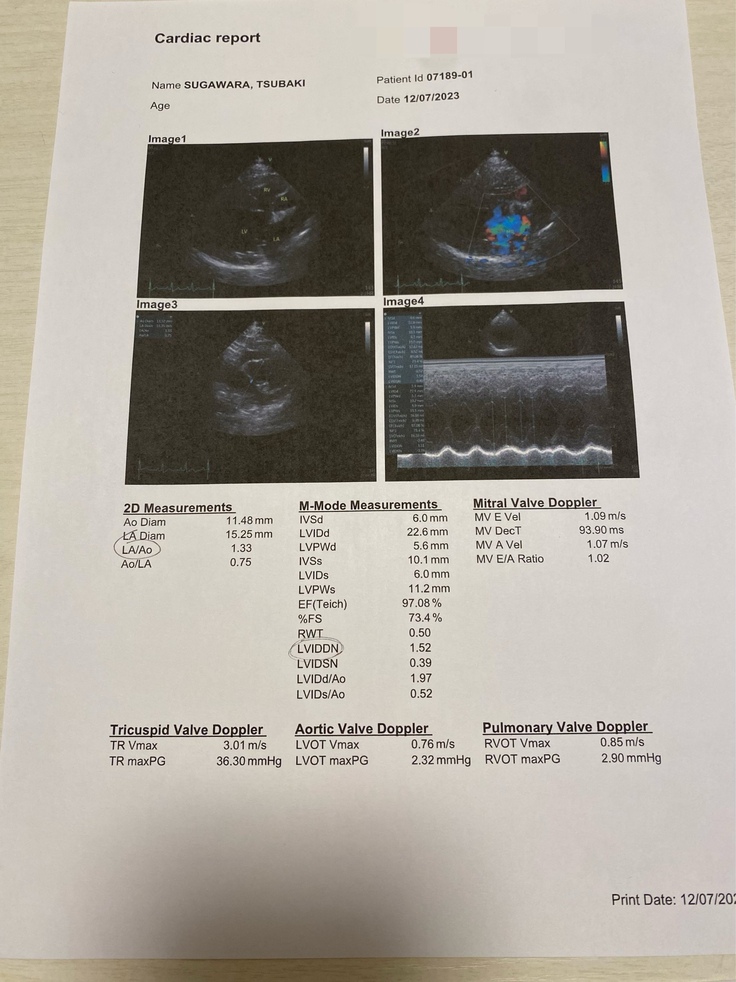

▼レントゲンの写真

エコー検査で心臓の動きを実際に先生と確認したところ、やはり弁にズレが生じ、上手く閉じることが出来ておらず血液が逆流しているとのことでした。

▼右上画像緑色の部分が逆流している血液